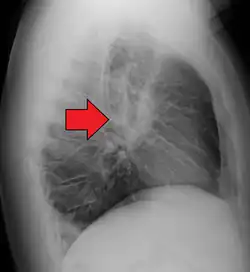

Chest X-ray showing the typical nodularity of sarcoidosis, predominantly in the hila of the lungs.